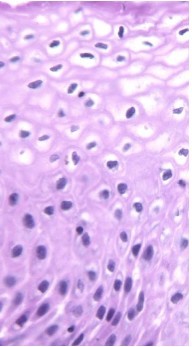

Normal Ectocervix

A young woman is in your office for a pap smear. Upon examining the cervix, you note that it is hyperemic and has points of focal erosion. On histologic specimen, this is what you see:

Chronic cervicitis: chronic exposure to bacteria in the vagina (STDs). Mucosa hyperemic, focal erosion visible, lymphocytes and plasma cells with germinal centers, squamous metaplasia.